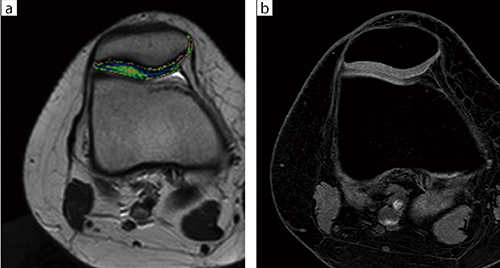

■症例3:膝蓋骨の亜脱臼疑い(ECHELON OVAL)

T2RELAX Mapにより膝蓋骨軟骨の変性がカラーマップにて評価できる(a)。

RSSG WEは薄いスライスにて描出できるため膝蓋骨軟骨の形態の把握に有用である(b)。

a:T2RELAX Map,AX,FOV:160,TR/TE:2000/12,スライス厚:4mm

b:3D RSSG,AX,FOV:160,TR/TE:16/7.4,FA:25°,スライス厚:1.1mm

”が搭載された。Soft Soundでは検査時のノイズを従来の1/10に低減可能で,同院でもバージョンアップによって利用が可能になった。Soft Soundの効果について加々美部長は,「撮像が始まってもほとんどわからないくらいの騒音レベルに抑えられています。撮像時間が長いMRI検査では,静かなことは大きなメリットです」と述べる。そのほか,同院では膝関節の自家培養軟骨移植術の評価にT2RELAX Mapを用いた撮像にも取り組んでいる。